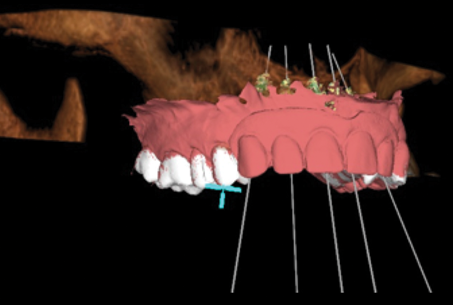

accomplished through therapeutic protocols utilizing osseointegrated dental implants and advanced ceramic prosthodontics to provide esthetically pleasing smiles.12 The treatment plan for this patient was implementation of a definitive prosthesis in the maxillary arch built on four implants-two in the anterior esthetic zone and two posterior tilted implants placed adjacent to the anterior wall of the sinus (Figure 8).

A fully integrated digital design was created focusing on the patient's desired outcomes of having a highly esthetic, natural-looking smile with ideal form and function that was as close to a natural dentition as possible. The smile design created using design software (3Shape Dental System, 3Shape, 3shape.com) and surface scanning images were merged with STL and CBCT files to engineer a virtual surgical plan, and then a pre-manufactured screw-retained fixed provisional restoration was fabricated-milled polymethyl methacrylate manufactured on a five-

axis mill (M5 Heavy Metal Milling Unit, Zirkonzahn, zirkonzahn.com)-that would function as the basis for the desired result (Figure 9 and Figure 10). The hypoplastic nature of the tissue and congenital deformity necessitated strict precision in the placement of the implants. Robotic guidance was employed to ensure the surgeon could make real-time plan adjustments if the bone or soft tissue contraindicated the treatment plan.

Fig 8. Digital treatment plan for Case 2 with implant positioning planned to optimize distribution for fully implant-supported fixed prosthetics that follow the ideal position for restorative emergence and prosthesis design.

Figure 8

Fig 9. Presurgical proposed implant positions in digital scan with proposed scanbodies inserted to enable fabrication of screw-retained fixed provisional restoration prior to surgery.

Figure 9

Fig 10. Maxillary and mandibular STL files of presurgical scans with proposed implant positions embedded into the files in design software, enabling design and milling of the provisional prostheses.

Figure 10